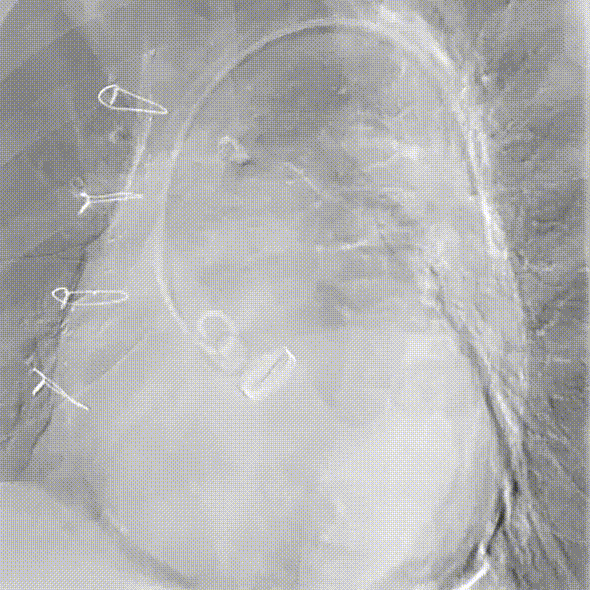

术前CT评估

术后CT评估